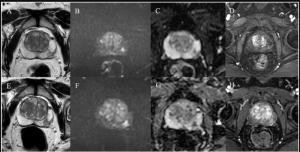

In a prospective study comparing PSMA PET/CT and mpMRI for biopsy- and imaging-naïve men with suspected prostate cancer (PCa), PSMA PET/CT led to altered management in 34 percent of confirmed cases of PCa.